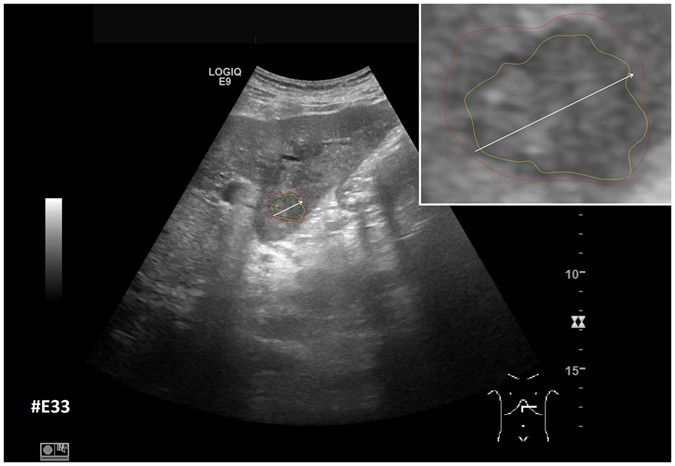

Figure 13

Example of a segmentation with a DSC of less than 80%. Depicted is the native image with a zoomed view of the metastasis (white box). The red outline represent the manual segmentation including the white arrow representing the manually drawn maximum diameter. The yellow outline represents the result of the semi-automatic segmentation.